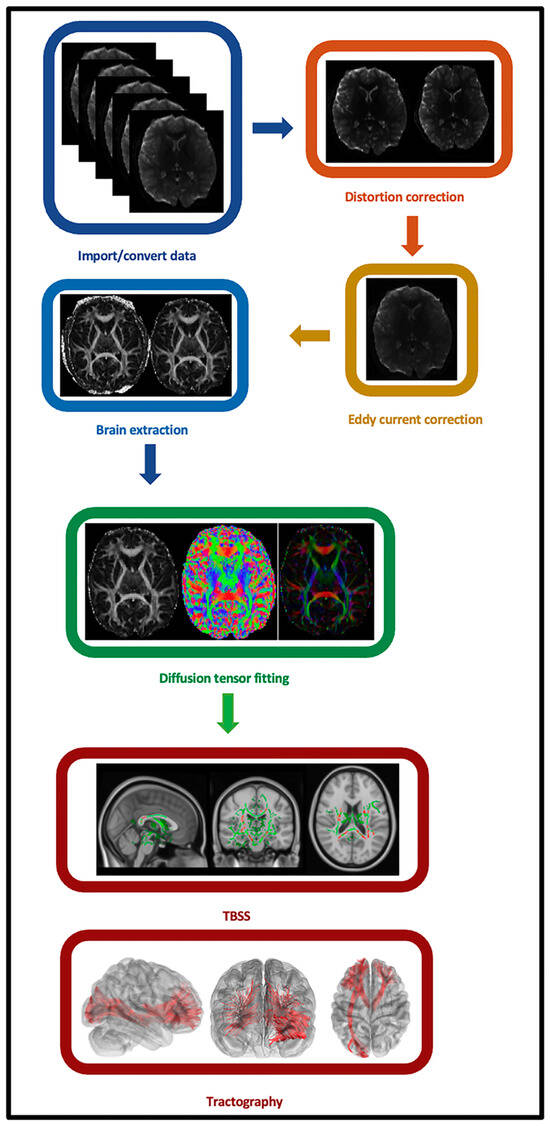

2.5. Individual-Level Imaging Data Preprocessing

2.6. Individual-Level Imaging Data Processing and Analyses

2.7. Secondary Tract-Based Spatial Statistics (TBSS) Analysis